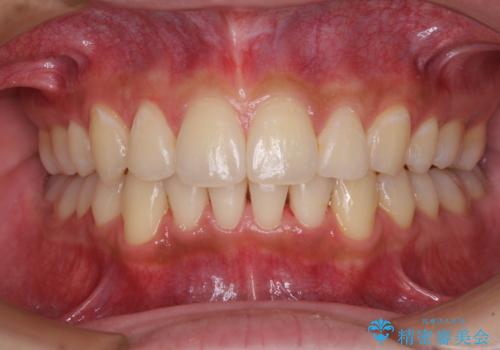

矯正治療の後戻りをインビザライン・ライトで解消

- 矯正治療の後戻りを気にして来院された患者様です。

後戻りは軽微であったので、インビザライン・ライトにより矯正治療を行うこととしました。

インビザライン・ライトは提供されるマウスピースの数に制限があり、通常のタイプよりもマウスピース提供期間が短くなっている一方、安価に治療を行うことができるプランです。

治療のゴールも変更できないため、軽微な歯列不正や、後戻り改善などに適しています。